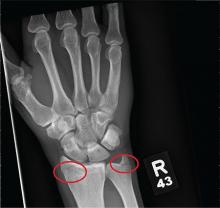

As you begin your shift, knowing deer season has started in your area, you wonder how long it will be before you see your first deer stand casualty of the day. With your first patient, you wonder no more: A 30-year-old man presents for evaluation of right wrist pain after falling from his deer stand. He says one of the straps holding the stand broke, causing him to fall forward and land on his outstretched hands. His medical history is unremarkable. Inspection of the right wrist shows no obvious deformity. No significant swelling is present. There is decreased range of motion and localized tenderness over the radius and ulna. Good pulses and capillary refill are noted. You obtain a radiograph of the wrist. What is your impression?

The radiograph shows a fracture of both the distal radius and distal ulna. The patient was placed in a splint and referred to orthopedics for outpatient follow-up.